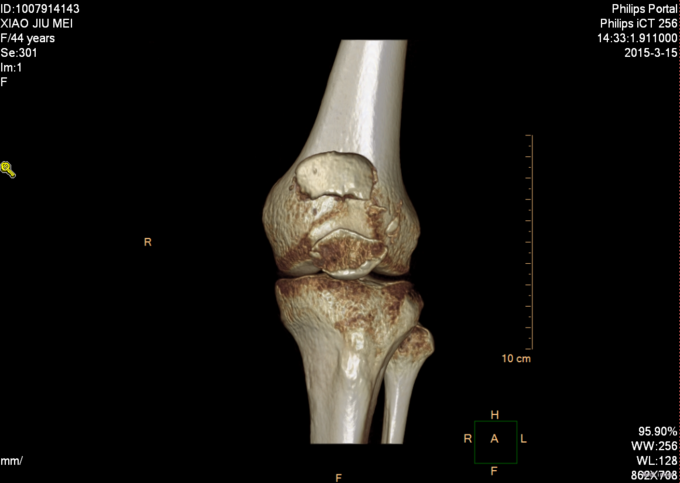

主诉:摔伤后左膝部疼痛肿胀活动受限4小时 患者及家属述患者于2015-3-14日9点40于自家不慎摔倒,导致左膝部疼痛肿胀活动受限,家人急送至沈阳市骨科医院,行DR检查示:左髌骨骨折。未行任何处理,现患者为求进一步诊治来我院,急诊以“左髌骨骨折”为主要诊断收入我科。患者自受伤以来,无发热,无呼吸困难,饮食睡眠正常,二便正常。

诊断:左髌骨骨折 患者入院后见患肢肿胀明显,给予患肢石膏固定抬高位,冷敷,甘露醇消肿等对症治疗,带患肢出现褶皱试验阳性后,CSEA下行左髌骨骨折切口复位张力带内固定术,术后患者肿胀明显,给予,消肿,冷敷,患肢抬高等对症治疗。患者每天换药观察切口愈合情况,无红肿及渗出,待伤口12天后予以拆线治疗,予以出院,给予康复处方。